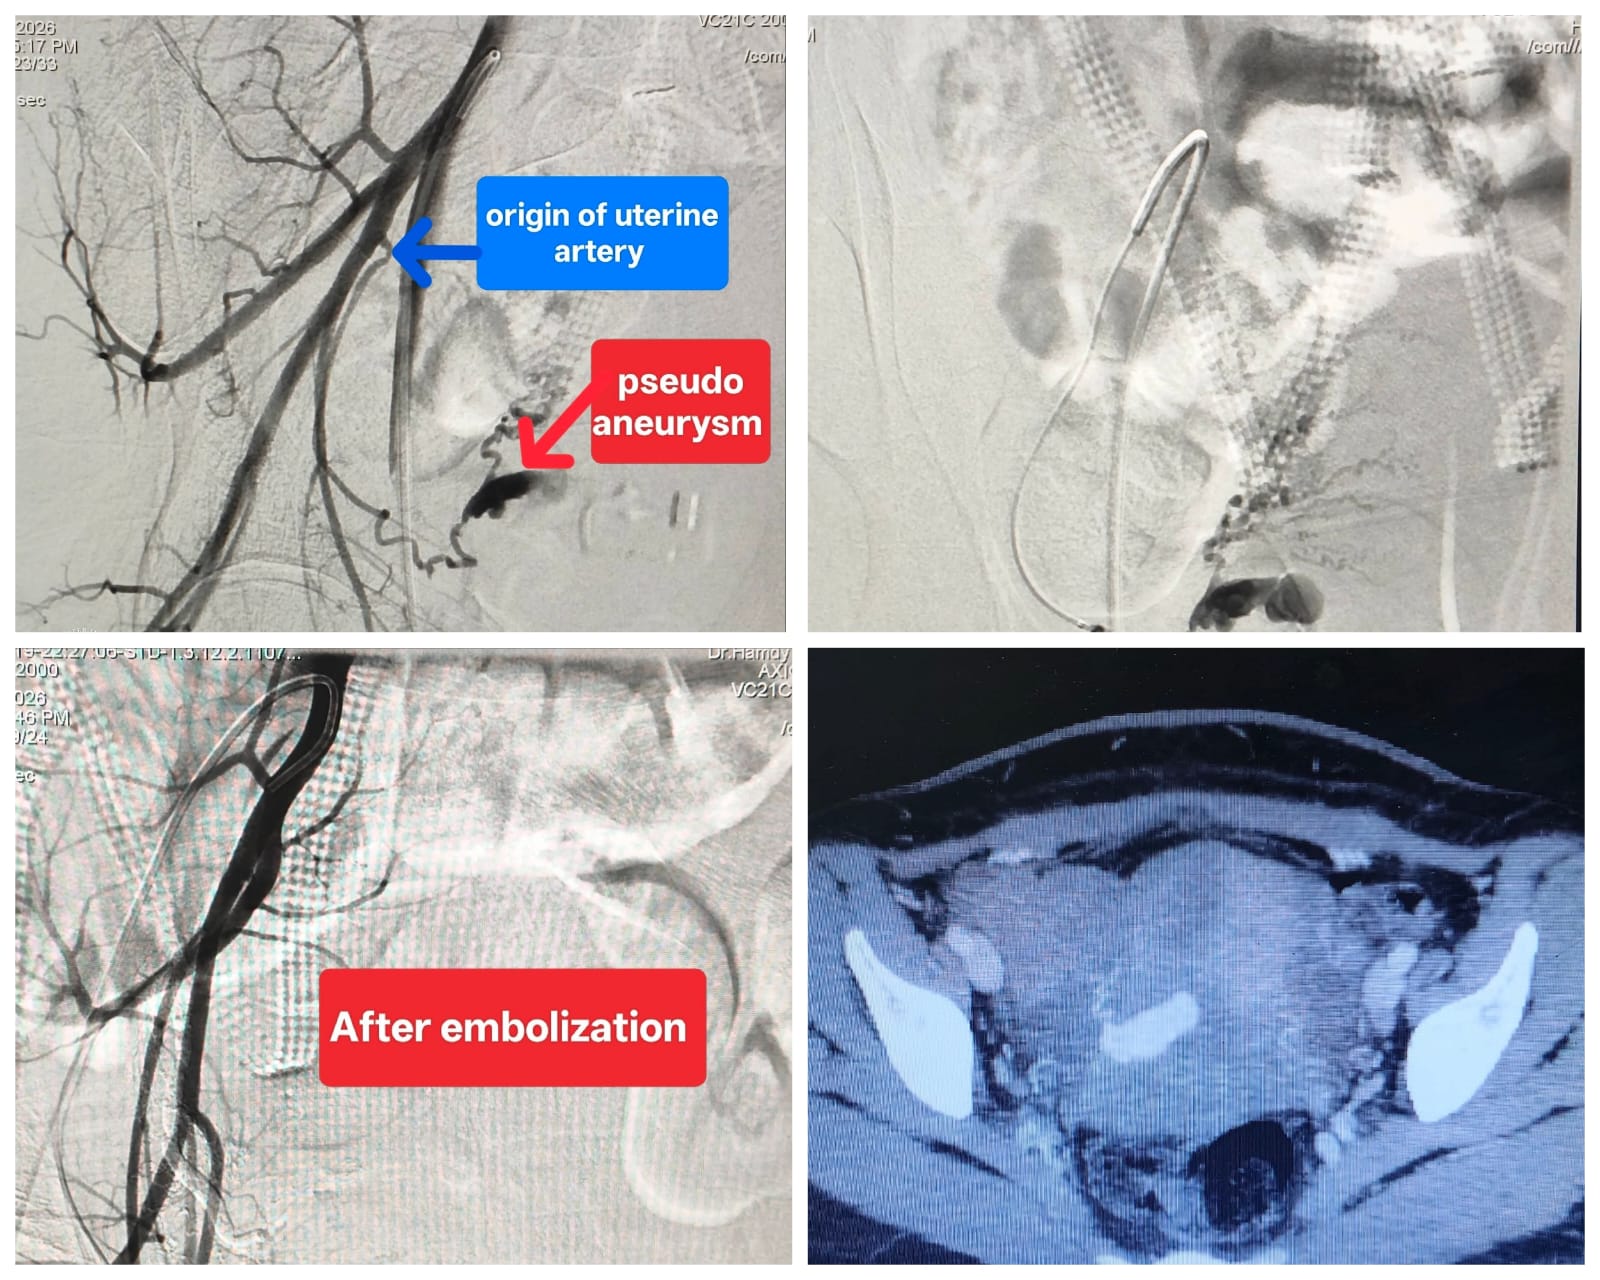

كان مستشفى صحة المرأة برئاسة الأستاذ الدكتور أحمد إبراهيم، قد استقبل سيدة تبلغ من العمر (٢٦) عاما، كانت تعاني من نزيف رحمي حاد أدى إلى هبوط حاد في الدورة الدموية، وذلك بعد مرور شهر على خضوعها لعملية ولادة قيصرية، وفور استقبال الحالة، تبين وجود نزيف مهبلي عنيف متكرر أدي لاضطراب العلامات الحيوية وتهديد حياة المريضة وبعد عمل أشعة مقطعية بالصبغة علي شرايين البطن والحوض تبين وجود ناسور شرياني وريدي وكيس دموي بالرحم، ليتم تحويل المريضة إلى قسم الأشعة التشخيصية والتدخلية بالمستشفى الرئيسي، وعلى الفور قام الفريق الطبي بإجراء تدخل دقيق باستخدام تقنيات الأشعة التدخلية لغلق الناسور و الكيس الدموي بنجاح تام في وقت قياسي ودون أي مضاعفات تذكر.

تدخل الفريق الطبي من قسم الأشعة التشخيصية والتدخلية والتصوير الطبي بقيادة الدكتور حمدي محمد إبراهيم، أستاذ مساعد الأشعة التدخلية، يعاونه الدكتور إبراهيم أيمن، استشاري الأشعة، تحت إشراف الأستاذ الدكتور مصطفى الشرقاوي، أستاذ الأشعة التدخلية ورئيس الفريق النوبتجي.

وأعلن الفريق الطبي أن الحالة شهدت تحسناً فورياً وملحوظاً في العلامات الحيوية، لتستقر حالة المريضة بعد ذلك، وتمت متابعتها حتي التحسن الكامل قبل مغادرة المستشفى.